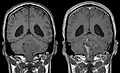

Épendymomes supratentoriels

Les épendymomes supratentoriels (SE) représentent entre 40% et 60% des tumeurs intracrâniennes. Localisées au niveau supratentoriel, ces tumeurs apparaissent comme des grosseurs peu homogènes, présentant des zones kystiques, des calcifications mais également des zones hémorragiques et nécrosées.

Aspect radiologique à l’IRM en séquence T1 après injection de Gadolinium d’un épendymome supratentoriel, caractérisé par une lésion bien délimitée du lobe frontal gauche avec prise de contraste hétérogène et des zones de nécrose.